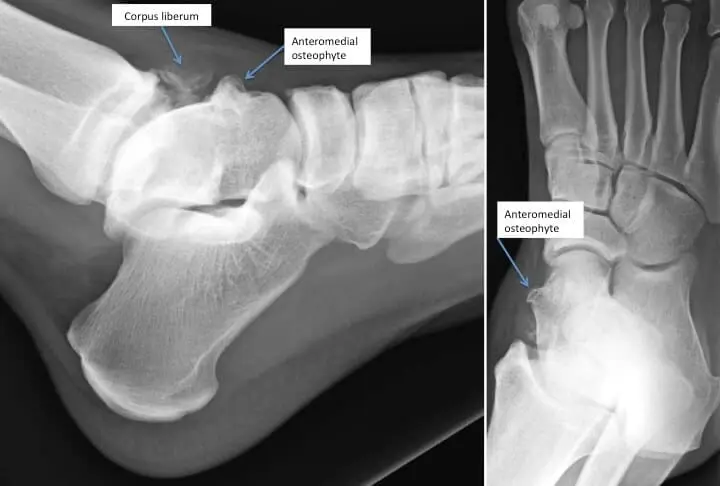

La douleur est due à une inflammation de certaines structures dans l’articulation qui sont irritées de façon chronique par des mouvements répétitifs, parfois consécutif à un traumatisme, comme une entorse banale ou une fracture de cheville. C’est la lésion typique et fréquente des footballeurs qui donnent de façon répétitive des coups de pied sur le côté interne de la cheville provoquant un excroissance osseuse au même niveau. Ce conflit osseux entraîne à son tour une inflammation des parties molles (capsule, synoviales…). Cependant, dans certains cas, l’excroissance osseuse (ostéophytes) est secondaire à l’arthrose sous-jacente au niveau de la cheville.

- La radiographie standard, toujours.

- Eventuellement un scanner avec parfois une injection de cortisone dans l’articulation ou si on recherche une lésion du cartilage ou des fragments libres